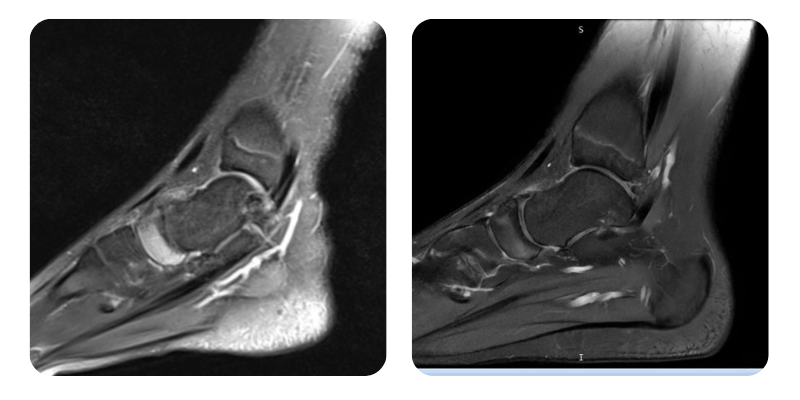

Prima

Dopo

M.M.T., 14 anni - Osteonecrosi asettica dello scafoide del piede sinistro, malattia di Lyme

Risultati: RMN del piede.

Evoluzione: Alla rivalutazione il paziente riferisce quasi completa scomparsa del dolore, ora circa 1/10 rispetto a 6-7/10 iniziali, con aumento della mobilita. Alla RMN di controllo si osserva una riduzione dell'edema di circa il 70%.